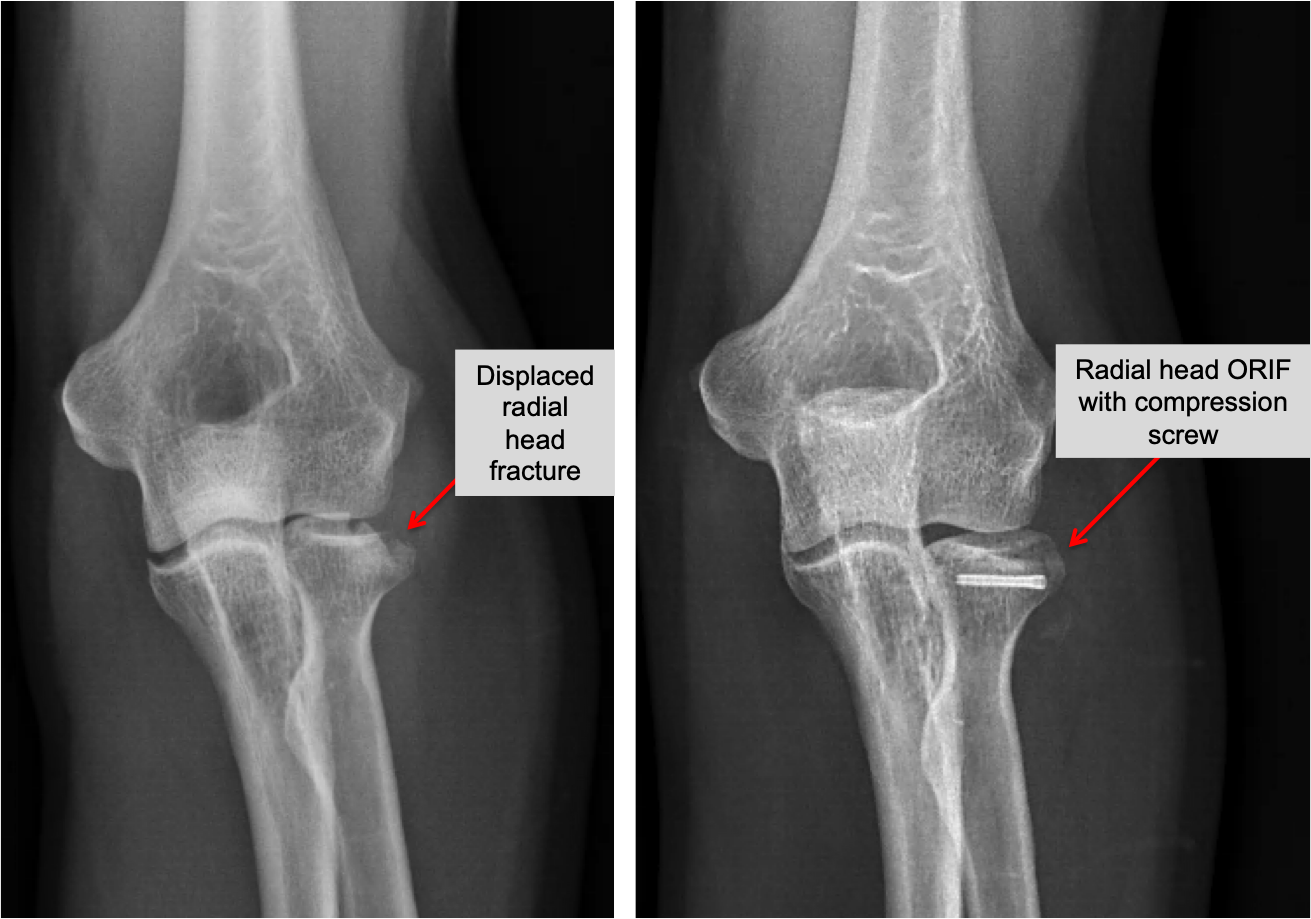

Radial Head Break Recovery Time - It can take 6 weeks for a radial head or neck fracture to heal completely. Most fractures heal without any problems in six to twelve weeks. During this time, don’t stress the joint with heavy lifting or.